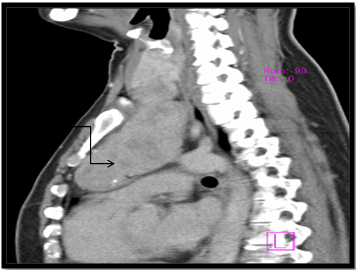

USG neck and CECT scan in view of retrosternal extension, revealed minimum extension of 8cm to maximum of 10cm. All retrosternal extension were descending to the anterior mediastinum, just abutting the level of aortic arch. The mass was causing mild tracheal luminal compromise in 03 cases and in the postero inferior aspect, the lesion was indenting and slightly displacing the aortic arch in 02 cases; however, the intervening fat planes were maintained. Laterally, the lesion was causing indentation of bilateral Internal Jugular Vein in all cases, 03 on right and 02 on left. Rest of the great vessels were normally visualised (Figure 3A, 3B & 3C).

Figure 3A CT image: Coronal section showing retrosternal extension of goiter (arrow).

Figure 3B CT image: Sagittal section showing retrosternal extension, approx. 10cm from superior most aspect of manubrium (arrow).

Figure 3C CT image: Axial section at the level of T2-T3 showing retrosternal extension of goitre upto the aortic arch (arrow).